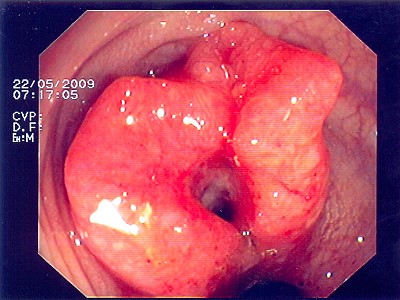

Abb. 1: Bösartiger Tumor des Übergangs von Mast- zu Dickdarm. Hier hilft ausschließlich eine Teilentfernung des Mast- und Dickdarmes. Abb. 1: Bösartiger Tumor des Übergangs von Mast- zu Dickdarm. Hier hilft ausschließlich eine Teilentfernung des Mast- und Dickdarmes.